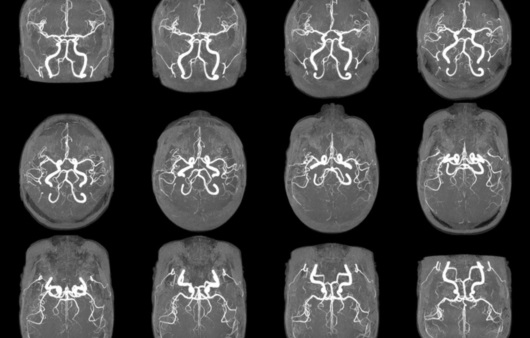

반면에 MRA(자기 공명 혈관 영상)는 MRI의 일종으로, 혈관의 이미지를 생성하는 데 초점을 맞추고 있습니다. 이는 혈관의 구조 및 흐름을 평가하는 데 유용하며, 주로 심혈관 질환의 진단에 사용됩니다. MRA는 특히 혈관의 협착이나 막힘, 동맥류와 같은 혈관 관련 문제를 발견하는 데 매우 유용합니다.

MRA는 MRI의 기법을 기반으로 하므로, 기본적으로는 동일한 작동 원리를 가지고 있지만, 약간의 차이점이 있습니다. MRA는 특히 혈관을 시각화하는 데 최적화되어 있으며, 주로 조영제를 사용하여 혈관을 더욱 뚜렷하게 구분합니다. 조영제는 혈관 내에서 신호의 차이를 만들어 신호 강도를 높여줍니다. 이로 인해 혈관의 형태와 상태를 더욱 명확하게 시각화할 수 있습니다.

- 혈관 질환의 조기 발견에 특화되어 있다.

- 비침습적인 방법으로 혈관 상태를 평가할 수 있다.

- 동맥류 및 혈관 협착의 평가

- 심혈관 질환 위험 환자의 혈관 상태 진단

- 선천적 심장 질환 및 혈관 기형의 확인